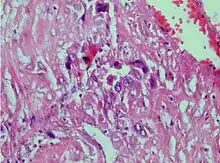

Photomicrograph showing proliferating intermediate trophoblast with scarce cytotophoblastic and syncytiotrophoblastic elements

A placental site trophoblastic tumor is a monophasic neoplasm of the implantation site intermediate trophoblast, and usually a benign lesion, which comprises less than 2% of all gestational trophoblastic proliferations. Preceding conditions include molar pregnancy (5%). Compared to choriocarcinoma or invasive mole, hemorrhage is less conspicuous and serum β-HCG level is low, making early diagnosis difficult.

Immunohistochemistry: Often stains with hPL, keratin, Mel-CAM, EGFR.